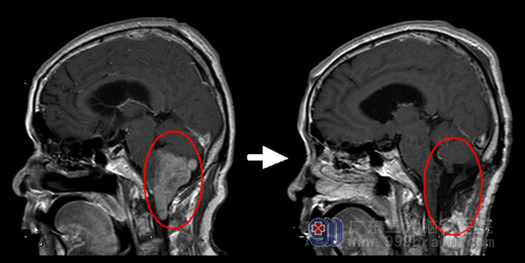

该院院长助理、综合神经外科主任鲁明接诊后,通过增强MRI进一步查明,骆先生双侧大脑后动脉异常改变,右侧枕骨大孔区有范围为5.0×4.4×3.8cm占位性病变,延髓、颈髓受压稍向前移位,第四脑室正中孔受压变窄,怀疑是室管膜瘤浸润脑干。

经过鲁明团队的分析,骆先生的肿瘤有全切的可能,而骆先生和家属也积极要求手术治疗。入院后第四天,鲁明主刀为骆先生行“延髓、第四脑室巨大占位切除术”。

鲁明表示,手术时可见灰褐色肿瘤组织,肿瘤基底部与副神经、舌咽神经、迷走神经粘连紧密,需要仔细分离才能切除。得益于精准的定位和电生理监测,骆先生的副神经、舌咽神经、迷走神经、小脑后下动脉均保留完整,顺利实现脑干区肿瘤全切。病理检查显示,室管膜瘤WHOII级,属良性,为防复发,骆先生还接受了放射治疗。

术后骆先生神志清醒,生命体征平稳,无后遗颅神经损害症状,眩晕头疼等症状消失。留院观察两周后康复出院。